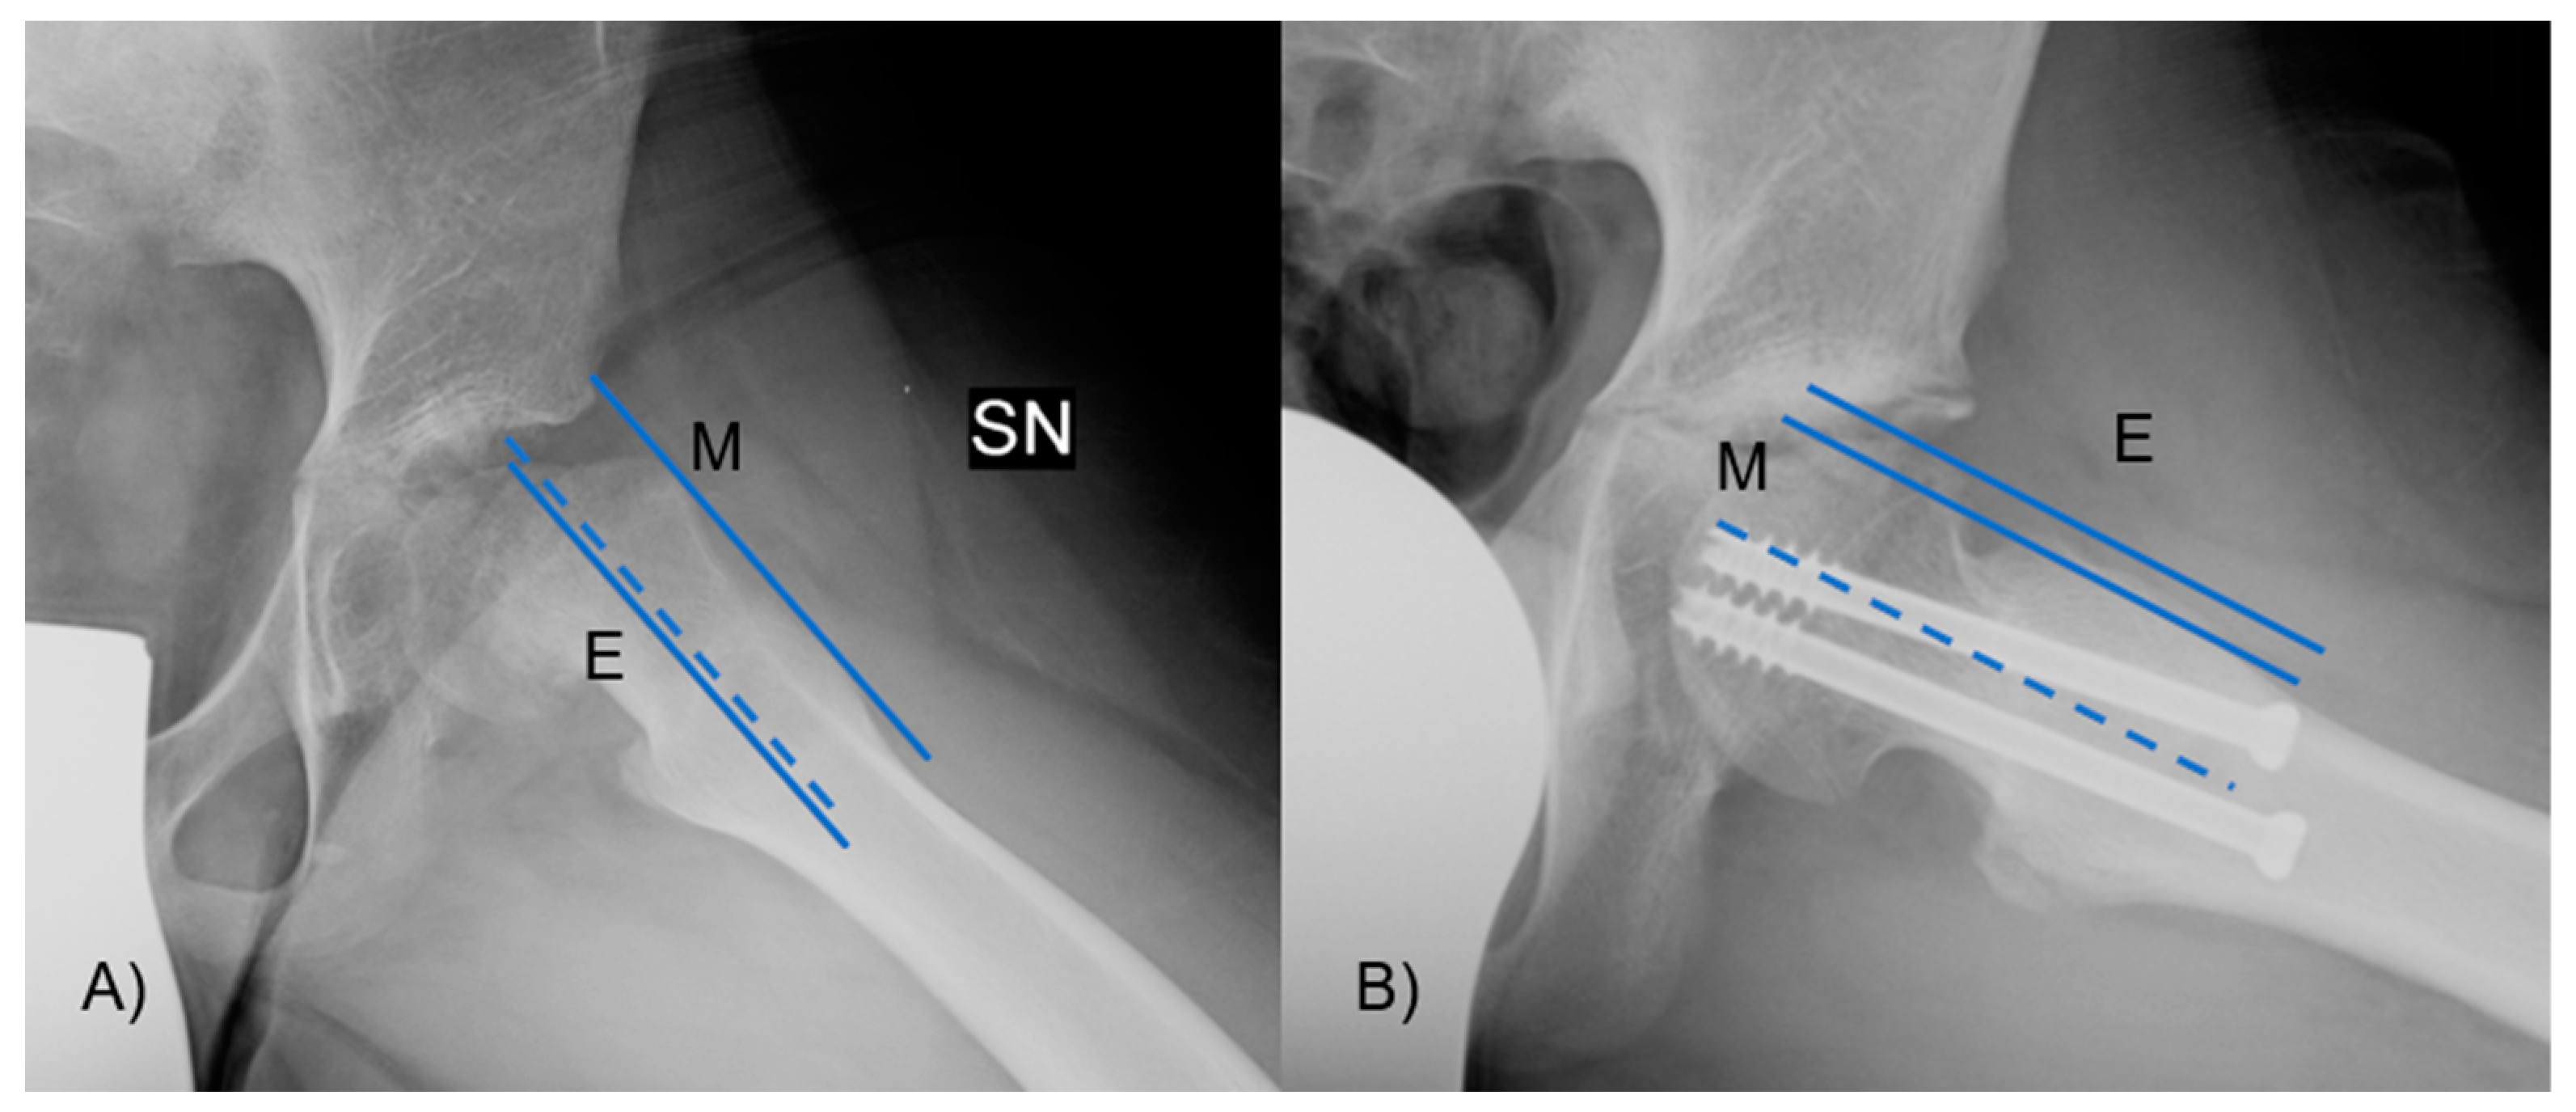

The α angle was measured between the axis of the femoral neck and the line extending from the central part of the femoral head to the location where the distance from the central point of the femoral head to the outer edge surpassed the femoral head’s radius (Figure 4). Slippage of the femoral head will occur at a higher α angle.

Figure 4.

The α angle was measured between the axis of the femoral neck and the line from the center of the femoral head to the point where the distance from the center of the femoral head to the peripheral contour of the femoral head exceeded the radius of the femoral head. In figure (A), there is an angle greater than 90°, with neck deformity, while in figure (B), the angle and the deformity are lessened.

The epiphyseal–metaphyseal offset was assessed in the frog-leg lateral view by determining the disparity between a line traced along the front border of the epiphysis, parallel to the femoral neck, and a line traced along the proximal–anterior edge of the metaphysis, also parallel to the femoral neck (Figure 5). A negative value means that the epiphysis lies posteriorly to the metaphysis. Finally, the presence of AVN or cartilage degeneration was evaluated at the latest available follow-up.

Figure 5.

The epiphyseal–metaphyseal offset was measured in the frog-leg lateral view as the difference between (E) a line drawn along the anterior edge of the epiphysis, parallel to the femoral neck, and (M) a line drawn along the proximal–anterior edge of the metaphysis, also parallel to the femoral neck. In figure (A) the offset is reduced due to the head slippage, while (B) after the reduction it is improved.